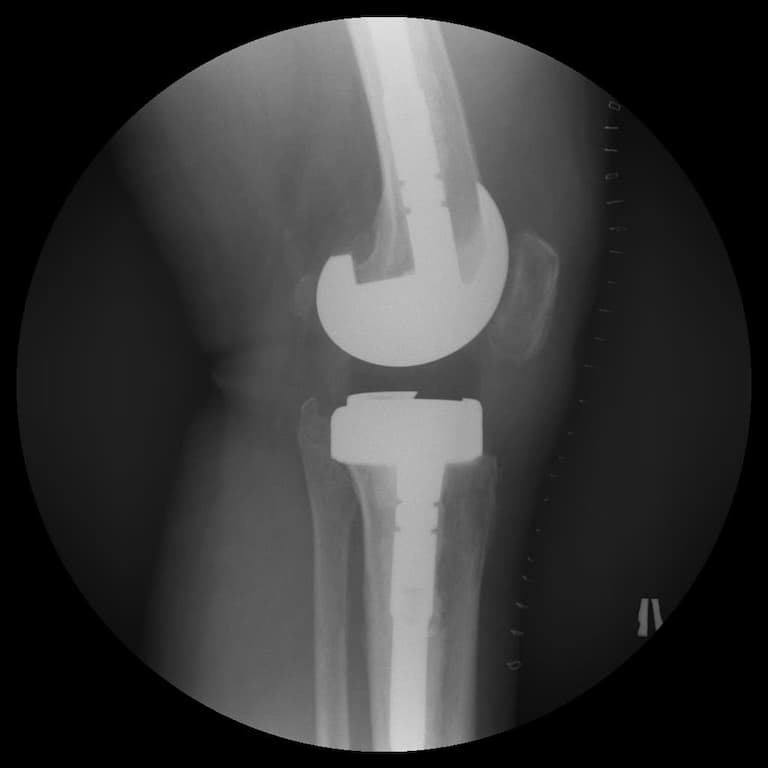

Үе дайрсан ясны анхдагч хавдар, ясны дутмагшлын үед хийгдэх мэс засалimg22Үе дайрсан ясны анхдагч хавдар, ясны дутмагшлын үед хийгдэх мэс засалimg23

Зураг 1. Сэргээн засах мэс заслын өмнөх рентген зураг. Эгц урд, хажуугаас авсан байдал.